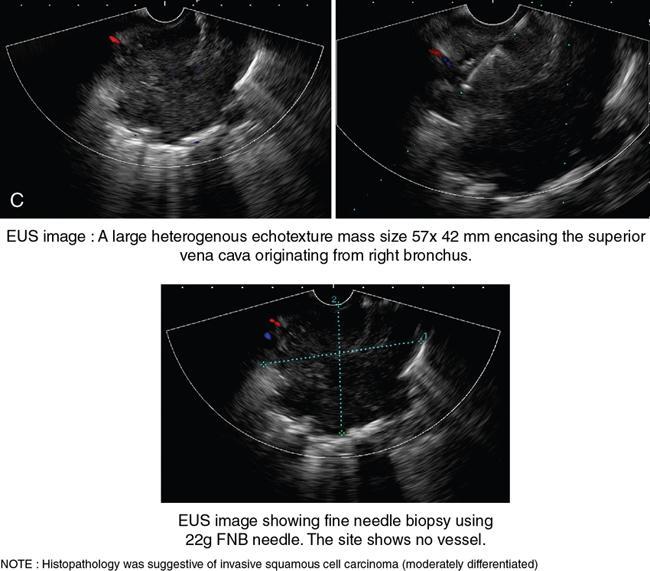

Role of endoscopic ultrasonography in oesophageal lesions (Fig. 8.1.6)

EUS in oesophageal cancer